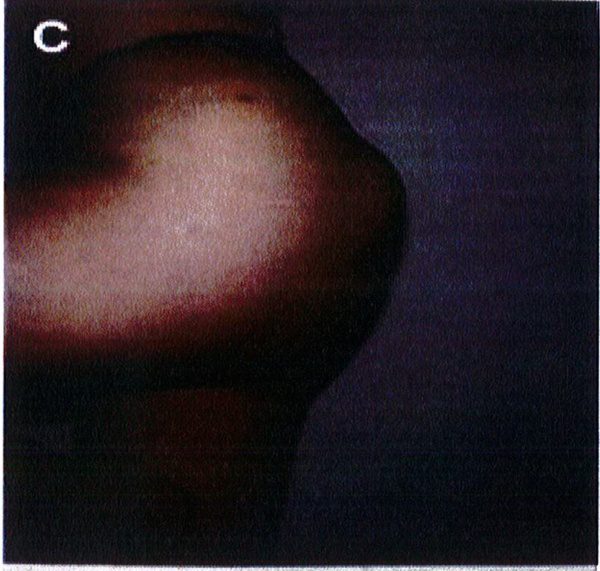

Kết quả phẫu thuật quan sát trên Hình. 3-5.

Hình. 3. (A-H) Tiền phẫu, chu phẫu và sau hậu phẫu 6 tháng của một bệnh nhân nữ 38 tuổi đươc ghép túi đôn mông với thể tích 330 cm3.

Hình. 4. (A-I) Hình ảnh tiền phẫu, chu phẫu và sau hậu phẫu 11 tháng của một phụ nữ 25 tuổi đã được thực hiện hút mỡ vùng éo, hông và sau xương vùng, đồng thời ghép khối cấy thể tích 270cm3.

Hình. 5. (A-F) Hình ảnh tiền phẫu và sau hậu phầu 4 tháng của bệnh nhân 67 tuổi, ghép khối implant thể tích 300 cm3.